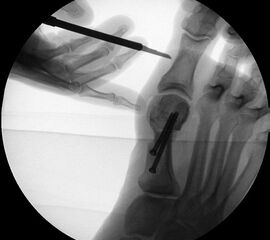

Abbildung 1

• Korrekturpotential größer als beim offenen Chevron, da die Gelenkkapsel als stabilisierendes Element erhalten bleibt und über eine trikortikale Osteosynthese mit zwei kanülierten Schrauben eine Verschiebung bis ca. 80% des Metatarsaledurchmessers möglich ist (Abb. 1).